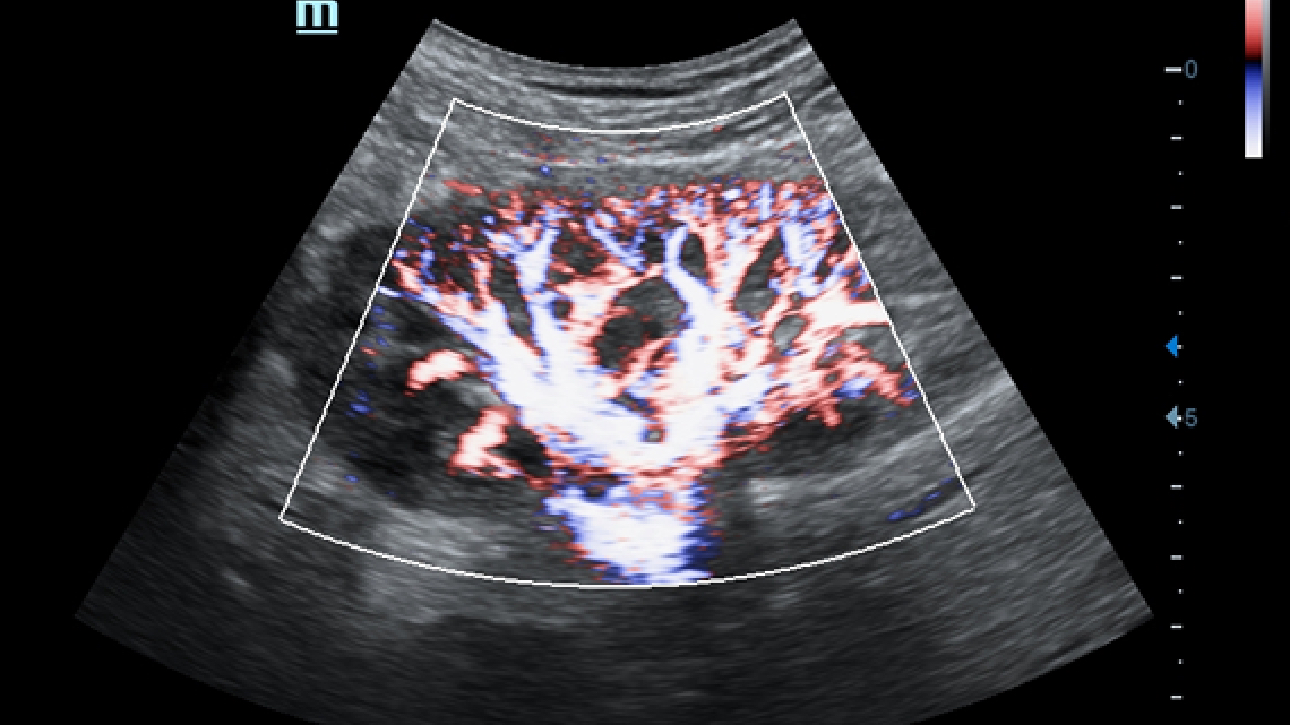

X-Insight ├© una soluzione completa studiata per offrire la migliore qualit├Ā diagnostica.

La nuova soluzione di Mindray ├© la traduzione pratica delle esigenze quotidiane dei clienti in soluzioni cliniche, il tutto con tecnologie ad ultrasuoni all'avanguardia ed in continua evoluzione.

Proponendosi come partner affidabile, DC-60 Exp con X-Insight si concentra su ci├▓ che conta veramente, semplificando la gestione della pratica clinica quotidiana con facilit├Ā e sicurezza.

Progettato per rispondere al meglio alle esigenze del cliente, DC-60 Exp con X-Insight ├© studiato per offrire un'efficienza elevata nel campo dell'imaging di precisione, grazie a una chiarezza immediata (eXpress Clarity), allŌĆÖeccezionale intelligenza (eXceptional Intelligence), oltre a vantare una lunghissima esperienza (eXceeding Experience).